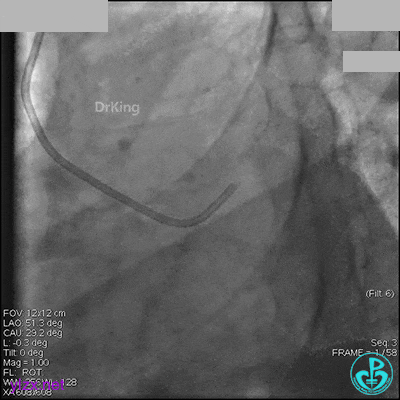

1周后再次上台,右冠脉3级血流,3段局限性严重狭窄,内膜模糊,应该是上次操作夹层遗留下的血肿。

先处理前降支开口严重狭窄并顺利植入前降支到左主干支架。